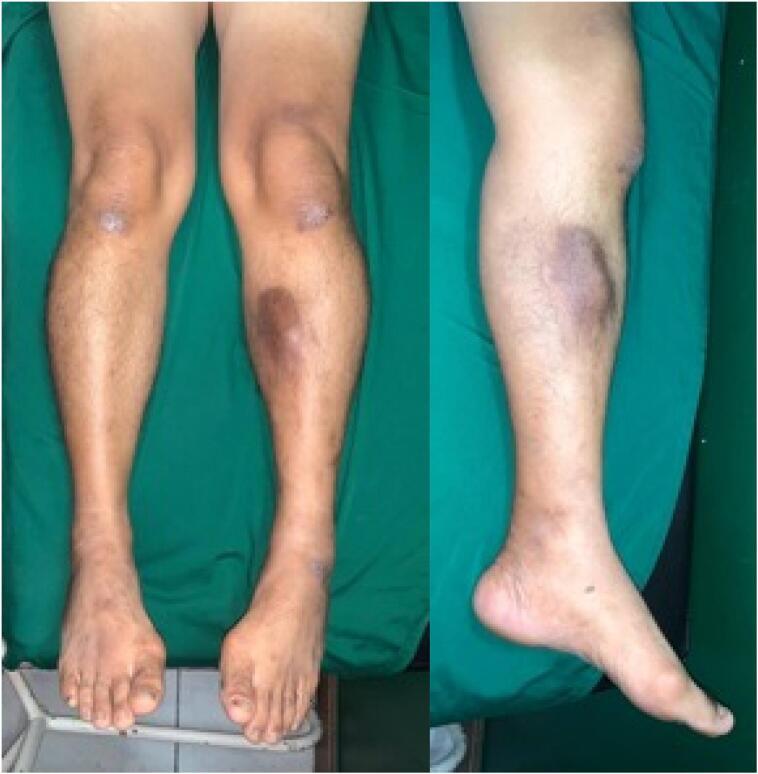

A male patient, 68 years old, came with complaint of a lump in the left cruris since one year ago. Nine months later, the lump has increased in size like a chicken egg and still felt painless. MRI result revealed a well-circumscribed multilocular cystic lesion in the peri-osseous soft tissue of the tibia. We performed directly excisional biopsy within the mass, and the histopathology result was periosteal ganglion cyst.